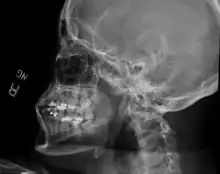

Bilateral anterior dislocation of the jaw

Jaw dislocation following relocation

CT image demonstrating jaw dislocation